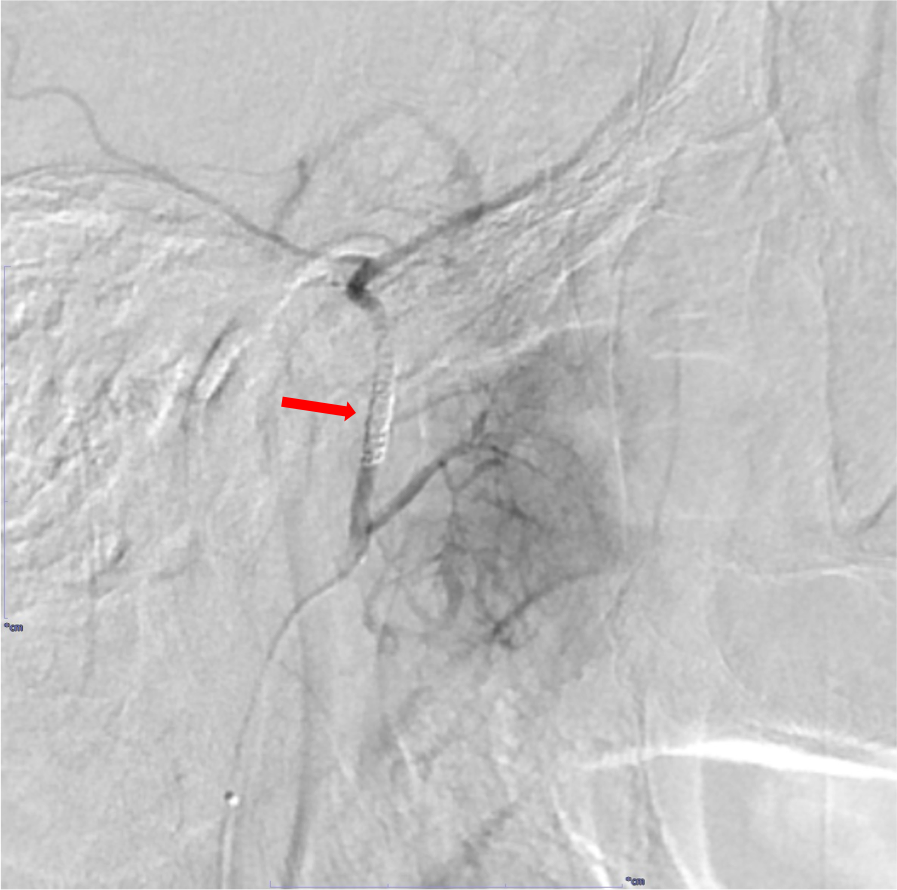

RADPLATは大量シスプラチンの超選択的動注化学療法と放射線治療の同時併用療法であり、局所制御の向上と臓器機能温存を期待できる。超選択的動注化学療法で癌の根治を目指す上で、腫瘍の進展範囲や栄養血管の同定、また周囲の重要構造物との関係やアクセスルートなど詳細な術前評価が不可欠であり、造影CTで解剖学的構造物を正確に描出することが求められる。

動脈相では動注化学療法のターゲットとなる血管や周囲の重要な血管を正確に描出することが求められるため、高容量のヨード造影剤を使用し、4.0ml/secの急速注入を行い、生理食塩水で後押しする。撮像タイミングはボーラストラッキング法を用いて決定するが、できるだけ純粋な動脈相を得ることが重要で、腫瘍や静脈の濃染が強くなると動脈の正確な評価が困難になる。このため、一般的な総頚動脈や中大脳動脈ではなく、大動脈弓にROIを設定する。

画像再構成は腫瘍の位置や血管走行を詳細に評価するため、0.5mmにスライス厚を設定する。各動脈、腫瘍を色分けしたVR像なども血管造影の際の支援画像として重要である。